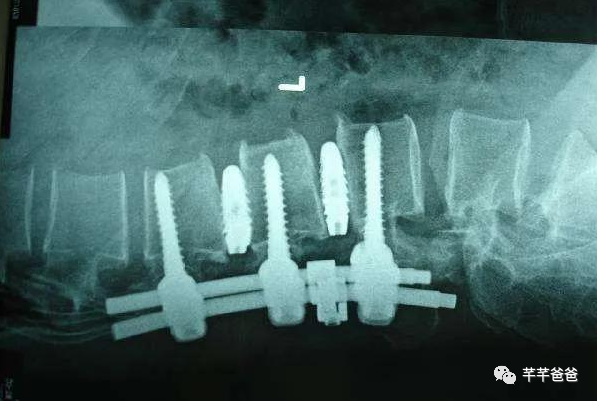

椎间盘融合手术,将几节突出的腰椎用钢钉进行融合,如下图,这样会导致弯腰受限,而且固定的这几节的压力会分摊到其他几节上,导致其他几节更容易突出;

(该图片源自网络)